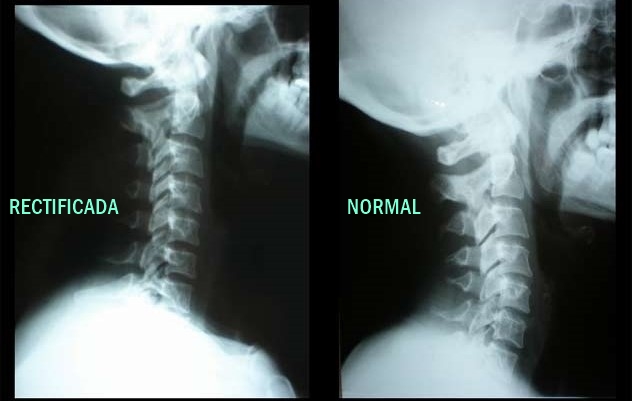

Quiropráctica

Corrección de columna, ajustes vertebrales y valoración postural para aliviar dolor de espalda, cuello y articulaciones.

Corrección postural

Alinea tu Columna